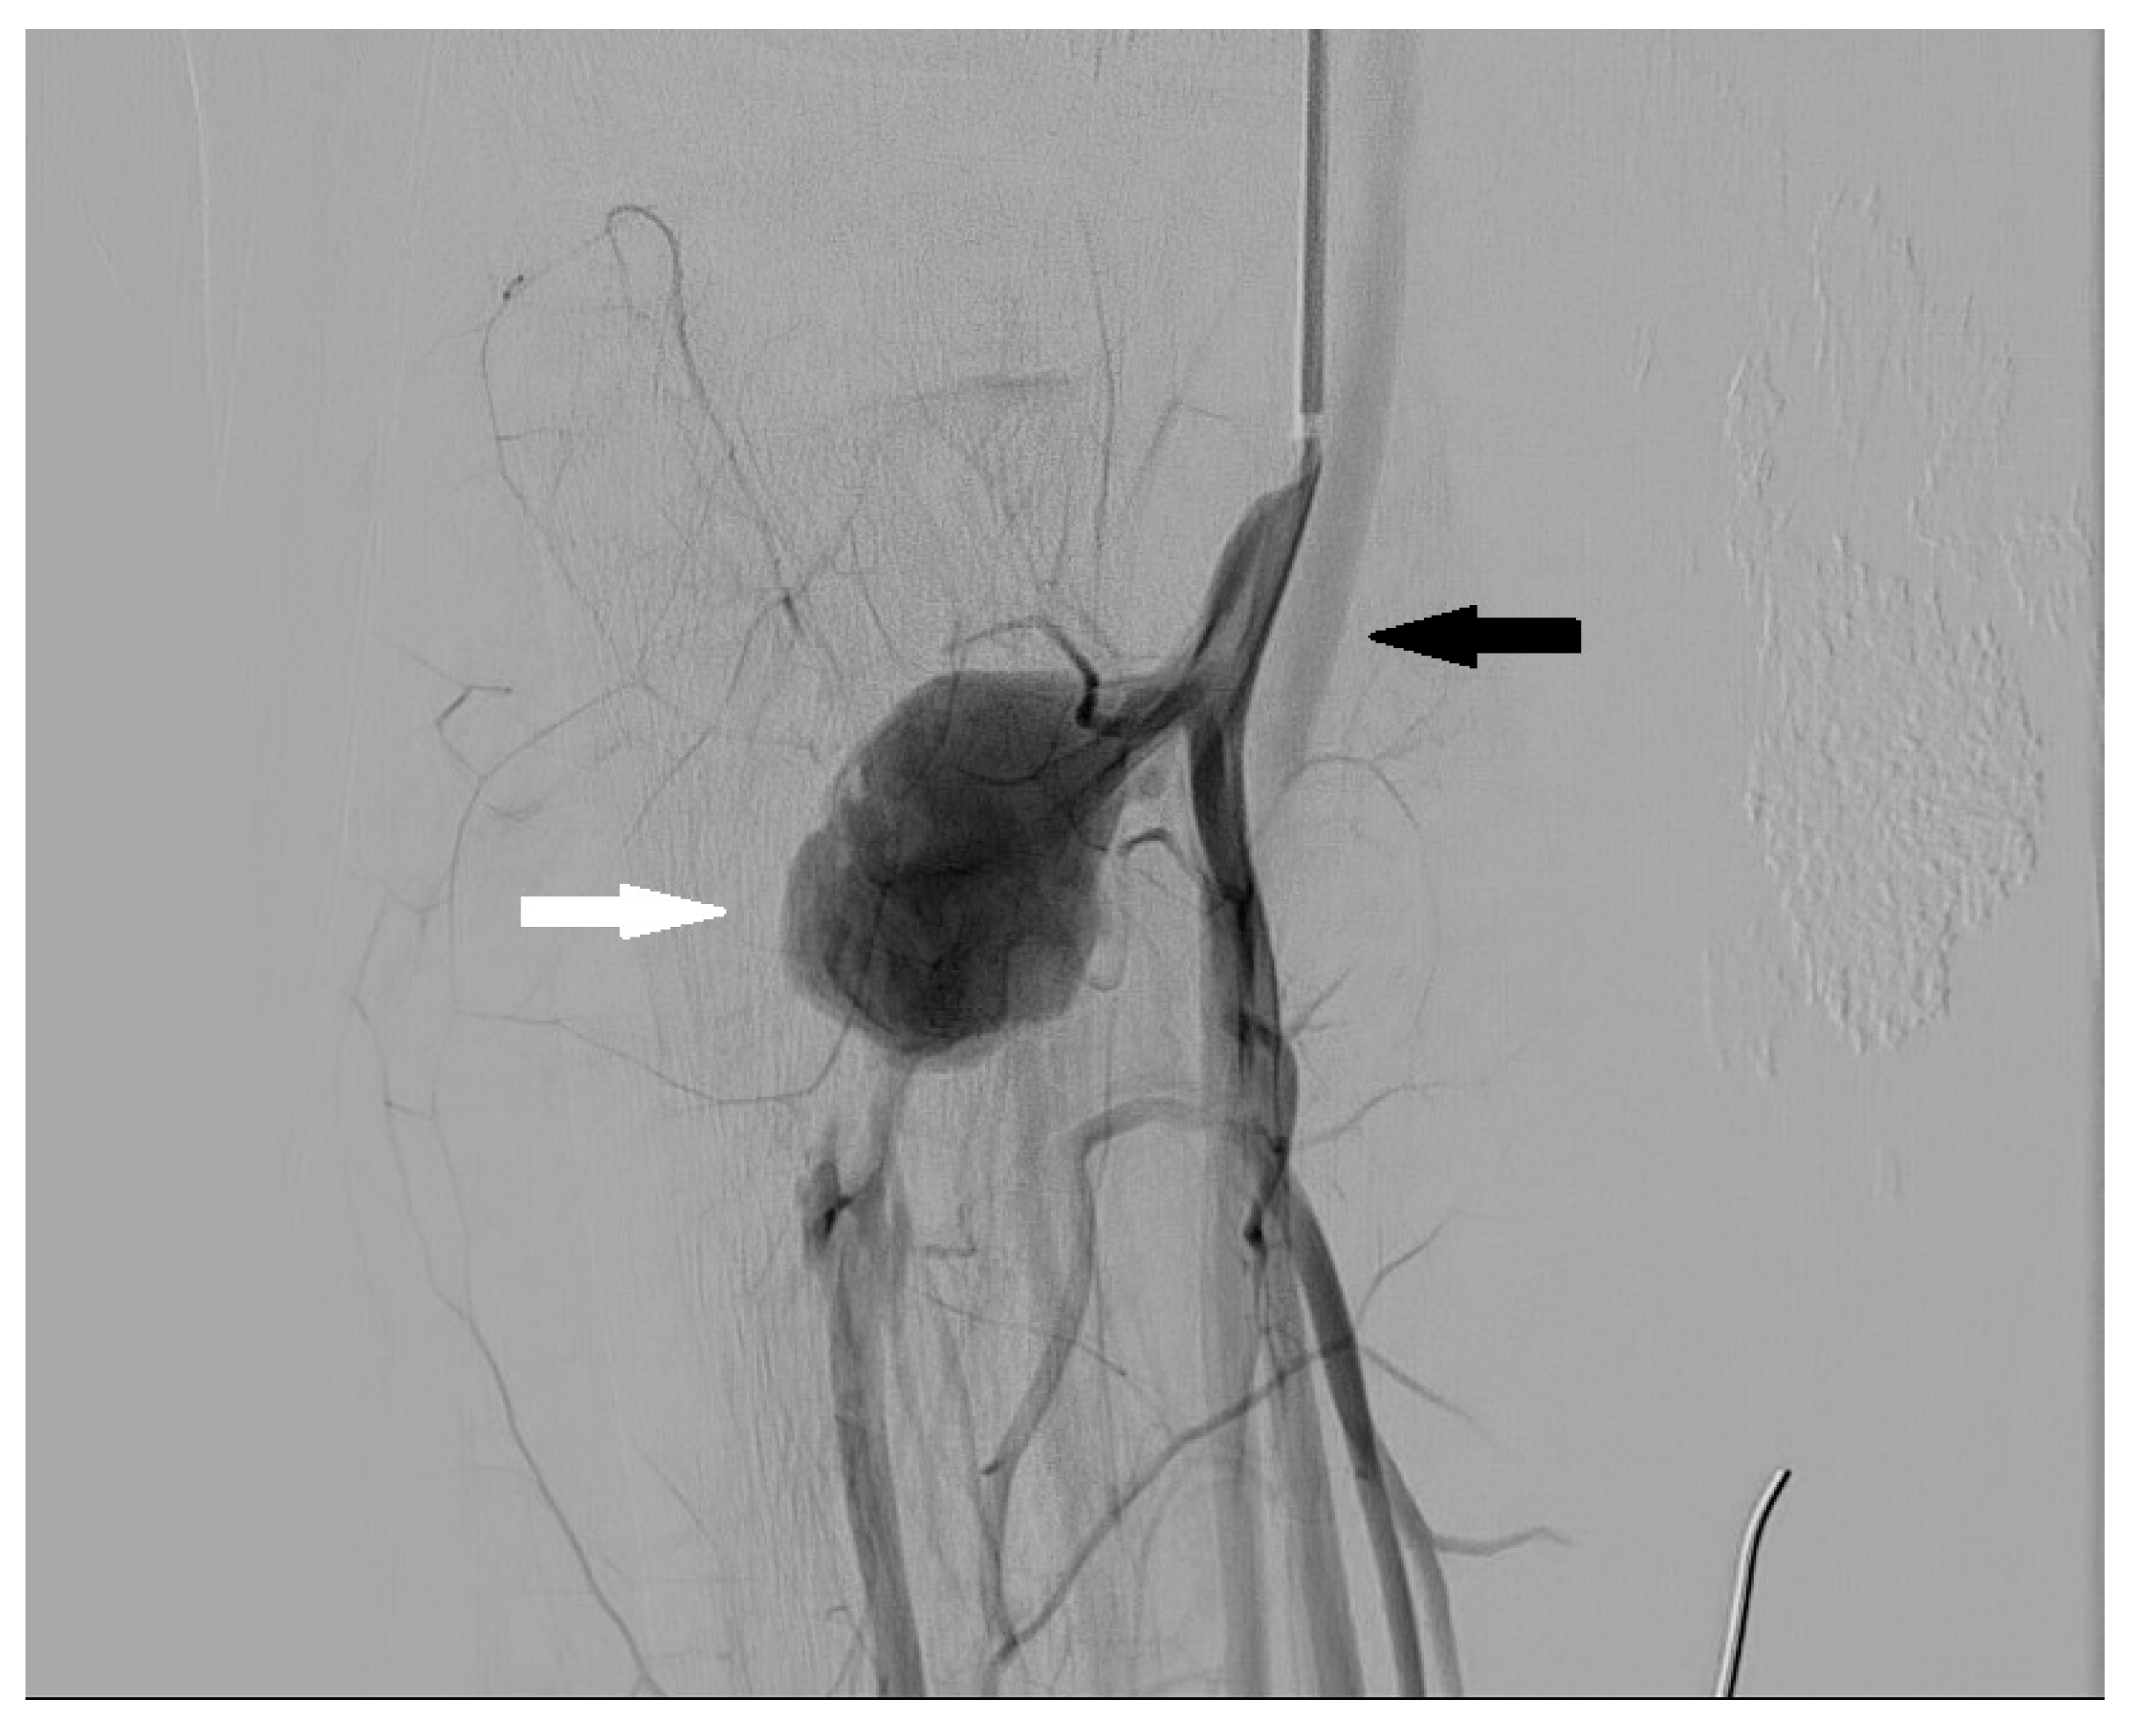

3.4. Aneurysm and Pseudoaneurysm